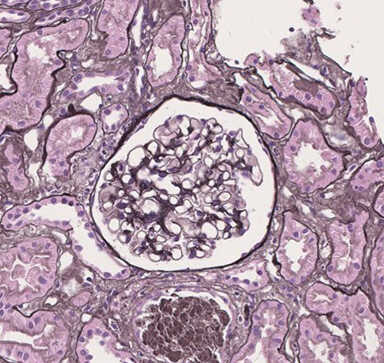

Histological Staining of Human Kidney Biopsy Samples

Data by courtesy of Dr. Furuhashi, Department of Nephrology, Nagoya University Graduate School of Medicine

Kidney tissue was collected using a 16 G biopsy gun and fixed with FM Fix (s) for one day at 4°C. After paraffin embedding and sectioning, hematoxylin and eosin (HE), periodic acid-Schiff (PAS), periodic acid-methenamine-silver (PAM), and Masson’s-trichrome (MT) staining were performed.

PAS

![[PAS] 10% Neutral buffered formalin](images/03340_img11.jpg)

![[PAS] FM Fix (s)](images/03340_img12.jpg)

[Result]

Tissue structure was better preserved with FM Fix (s) than with 10% neutral buffered formalin.